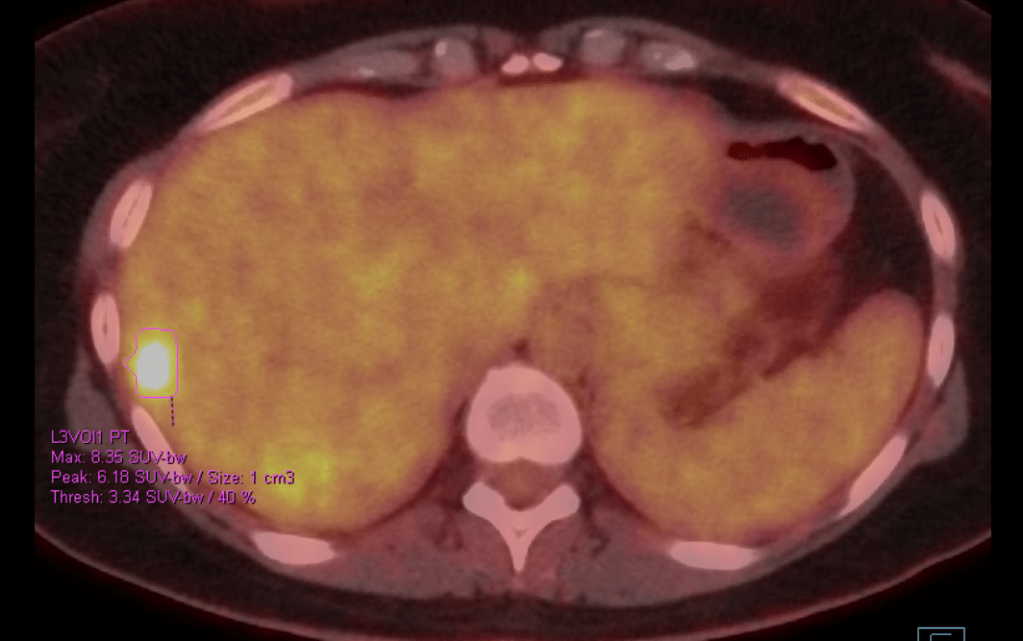

I’m starting this blog because I may be at a point now where this study starts to pay off. My most recent scan showed spots of hyperactivity in my liver, and it’s almost surely my cancer that is finally ready to make itself known again.

Screenshot of PET scan showing a 1cm bright spot on the liver

My oncologist wouldn’t say that it’s probably cancer. I know she was thinking it, though. And I know she would have said it if it wasn’t for the fact that something similar happened in January with some lymph nodes. “What else could it be if it’s not cancer?” my husband had asked. My oncologist replied very straightforwardly, “It’s not likely to be anything else”. But then they did a biopsy and didn’t find any cancer. Just some proliferating lymphocytes. She doesn’t act embarassed by this, but she must be if she is not saying that it is most likely cancer now. An oncologist wouldn’t order a biopsy if they really thought it was likely to be anything else. I’m not fooled for one second.